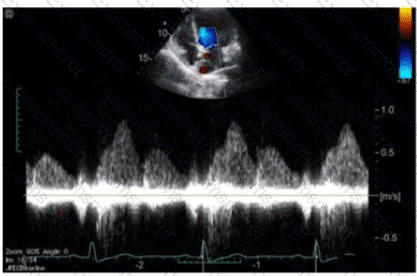

Which of the following does this Image represent?